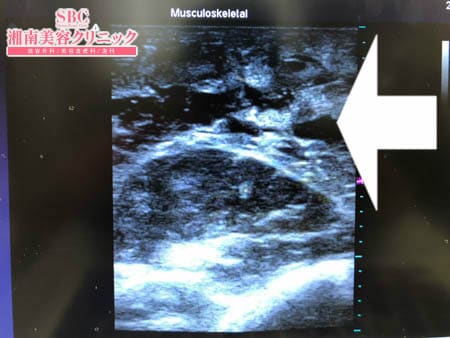

今回は力こぶ側の脂肪吸引の模様を

見ていただこうと思います。

いつものように3Dタッチビュー(超音波)で

皮下脂肪層を評価してみましょう。

画像でも分かるように

やはり大量の皮下脂肪が

ついていたわけではありませんが

その少ない皮下脂肪であっても

徹底的に根こそぐ!

というのが根こそぎ竹田先生の醍醐味。